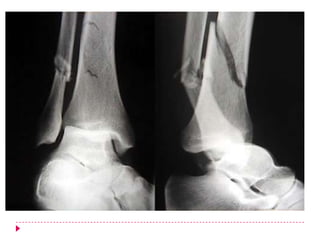

Definición “Fractura de Tobillo”

Fractura que involucra uno, dos o incluso los 3 huesos

que conforman la articulación del tobillo.

Epidemiología

   Unimaleolares 66%

   Bimaleolares 25%

   Trimaleolares 7%

   Abiertas 2%

   Pueden ser:

   Unimaleolares  maléolo medial o del peroneo

   Bimaleolares  ambos maléolos

   Trimaleorales  maléolo posterior (reborde posterior de la tibia)